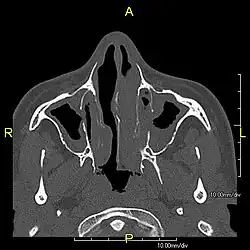

| Complications | Chronic recurrent respiratory infections, including sinusitis, bronchitis, pneumonia, and otitis media.[2] |

Around 80% of people with primary ciliary dyskinesia experience respiratory problems beginning within a day of birth. Many have a collapsed lobe of the lung and blood oxygen low enough to require treatment with supplemental oxygen.[1] Within the first few months of life, most develop a chronic mucus-producing cough and runny nose.[1] The main consequence of impaired ciliary function is reduced or absent mucus clearance from the lungs, and susceptibility to chronic recurrent respiratory infections, including sinusitis, bronchitis, pneumonia, and otitis media. Progressive damage to the respiratory system is common, including progressive bronchiectasis beginning in early childhood, and sinus disease (sometimes becoming severe in adults). However, diagnosis is often missed early in life despite the characteristic signs and symptoms.[2] In males, immotility of sperm can lead to infertility, although conception remains possible through the use of in vitro fertilization, there also are reported cases where sperm were able to move.[8] Trials have also shown that there is a marked reduction in fertility in females with Kartagener's syndrome due to dysfunction of the oviductal cilia.[9]

Many affected individuals experience hearing loss and show symptoms of otitis media which demonstrates variable responsiveness to the insertion of myringotomy tubes or grommets. Some patients have a poor sense of smell, which is believed to accompany high mucus production in the sinuses (although others report normal – or even acute – sensitivity to smell and taste). Clinical progression of the disease is variable, with lung transplantation required in severe cases. Susceptibility to infections can be drastically reduced by an early diagnosis. Treatment with various chest physiotherapy techniques has been observed to reduce the incidence of lung infection and to slow the progression of bronchiectasis dramatically. Aggressive treatment of sinus disease beginning at an early age is believed to slow long-term sinus damage (although this has not yet been adequately documented). Aggressive measures to enhance clearance of mucus, prevent respiratory infections, and treat bacterial superinfections have been observed to slow lung-disease progression. The predicted incidence is 1 in approximately 7500.[10]

Several diagnostic tests for this condition have been proposed.[5] These include nasal nitric oxide levels as a screening test, light microscopy of biopsies for ciliary beat pattern and frequency and electron microscopic examination of dynein arms, as the definite diagnosis method. Genetic testing has also been proposed but this is difficult given that there are multiple genes involved.[6]

When accompanied by the combination of situs inversus (reversal of the internal organs), chronic sinusitis, and bronchiectasis, it is known as Kartagener syndrome[3] (only 50% of primary ciliary dyskinesia cases include situs inversus).[11]